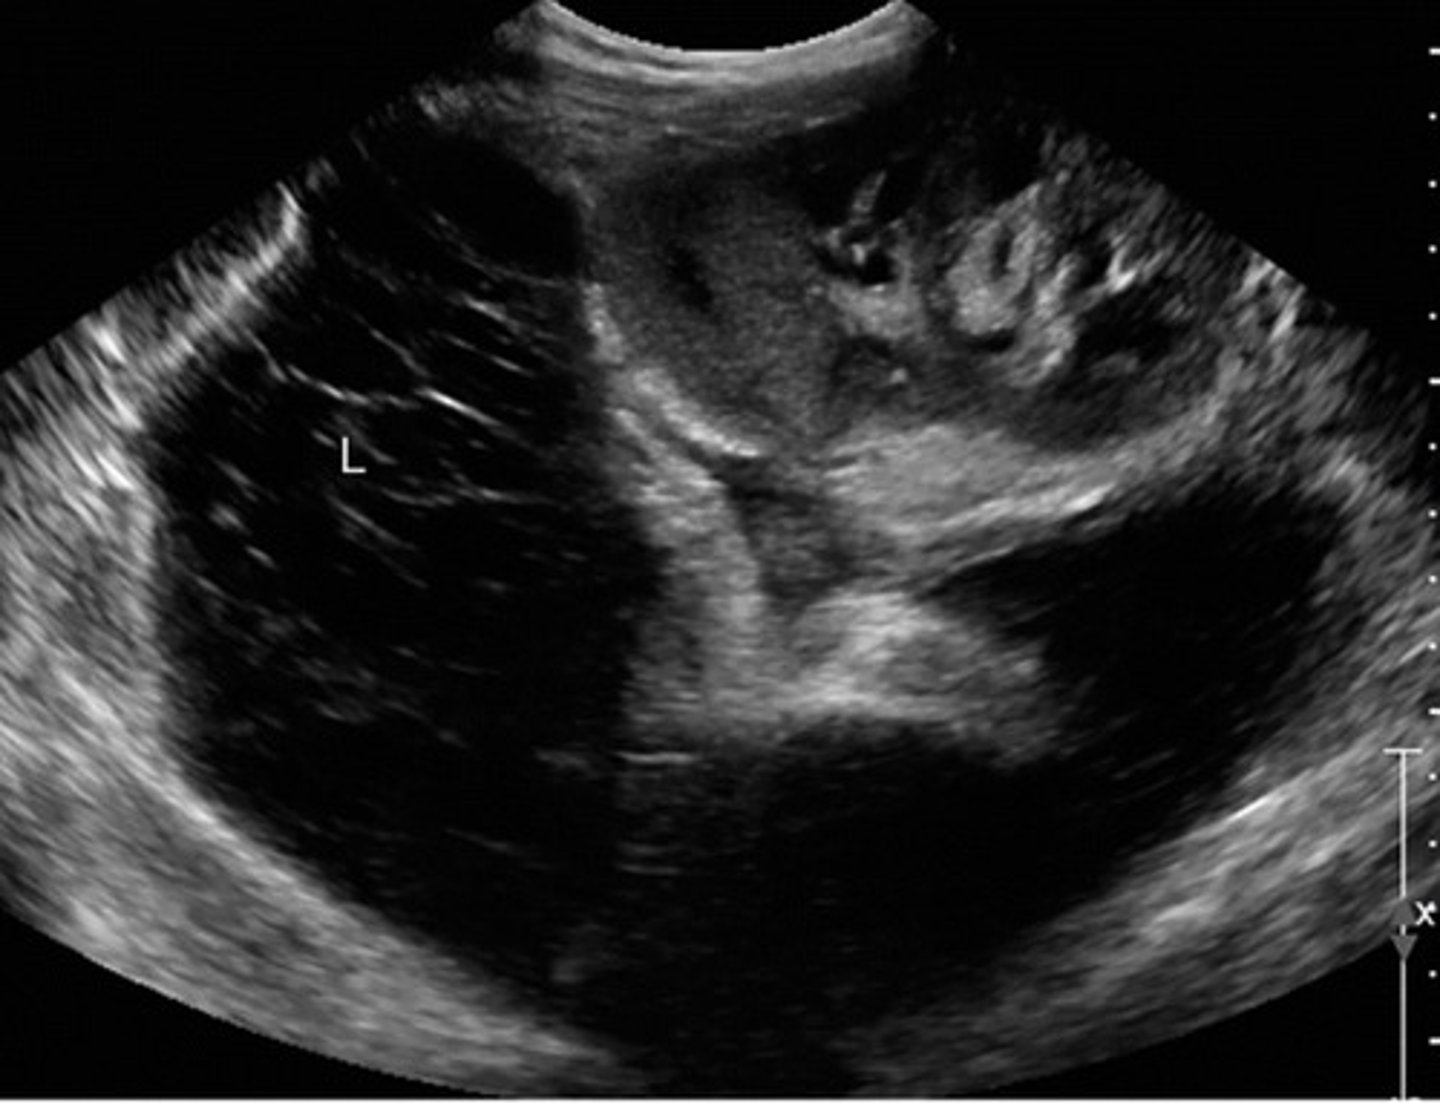

Cavernous Transformation

Due to chronic portal vein thrombosis

Occurs within 6 days after thrombotic event

Absent portal vein flow

Formation of new peri-portal vessels around portal vein

Hepatopetal flow within serpentine vessels